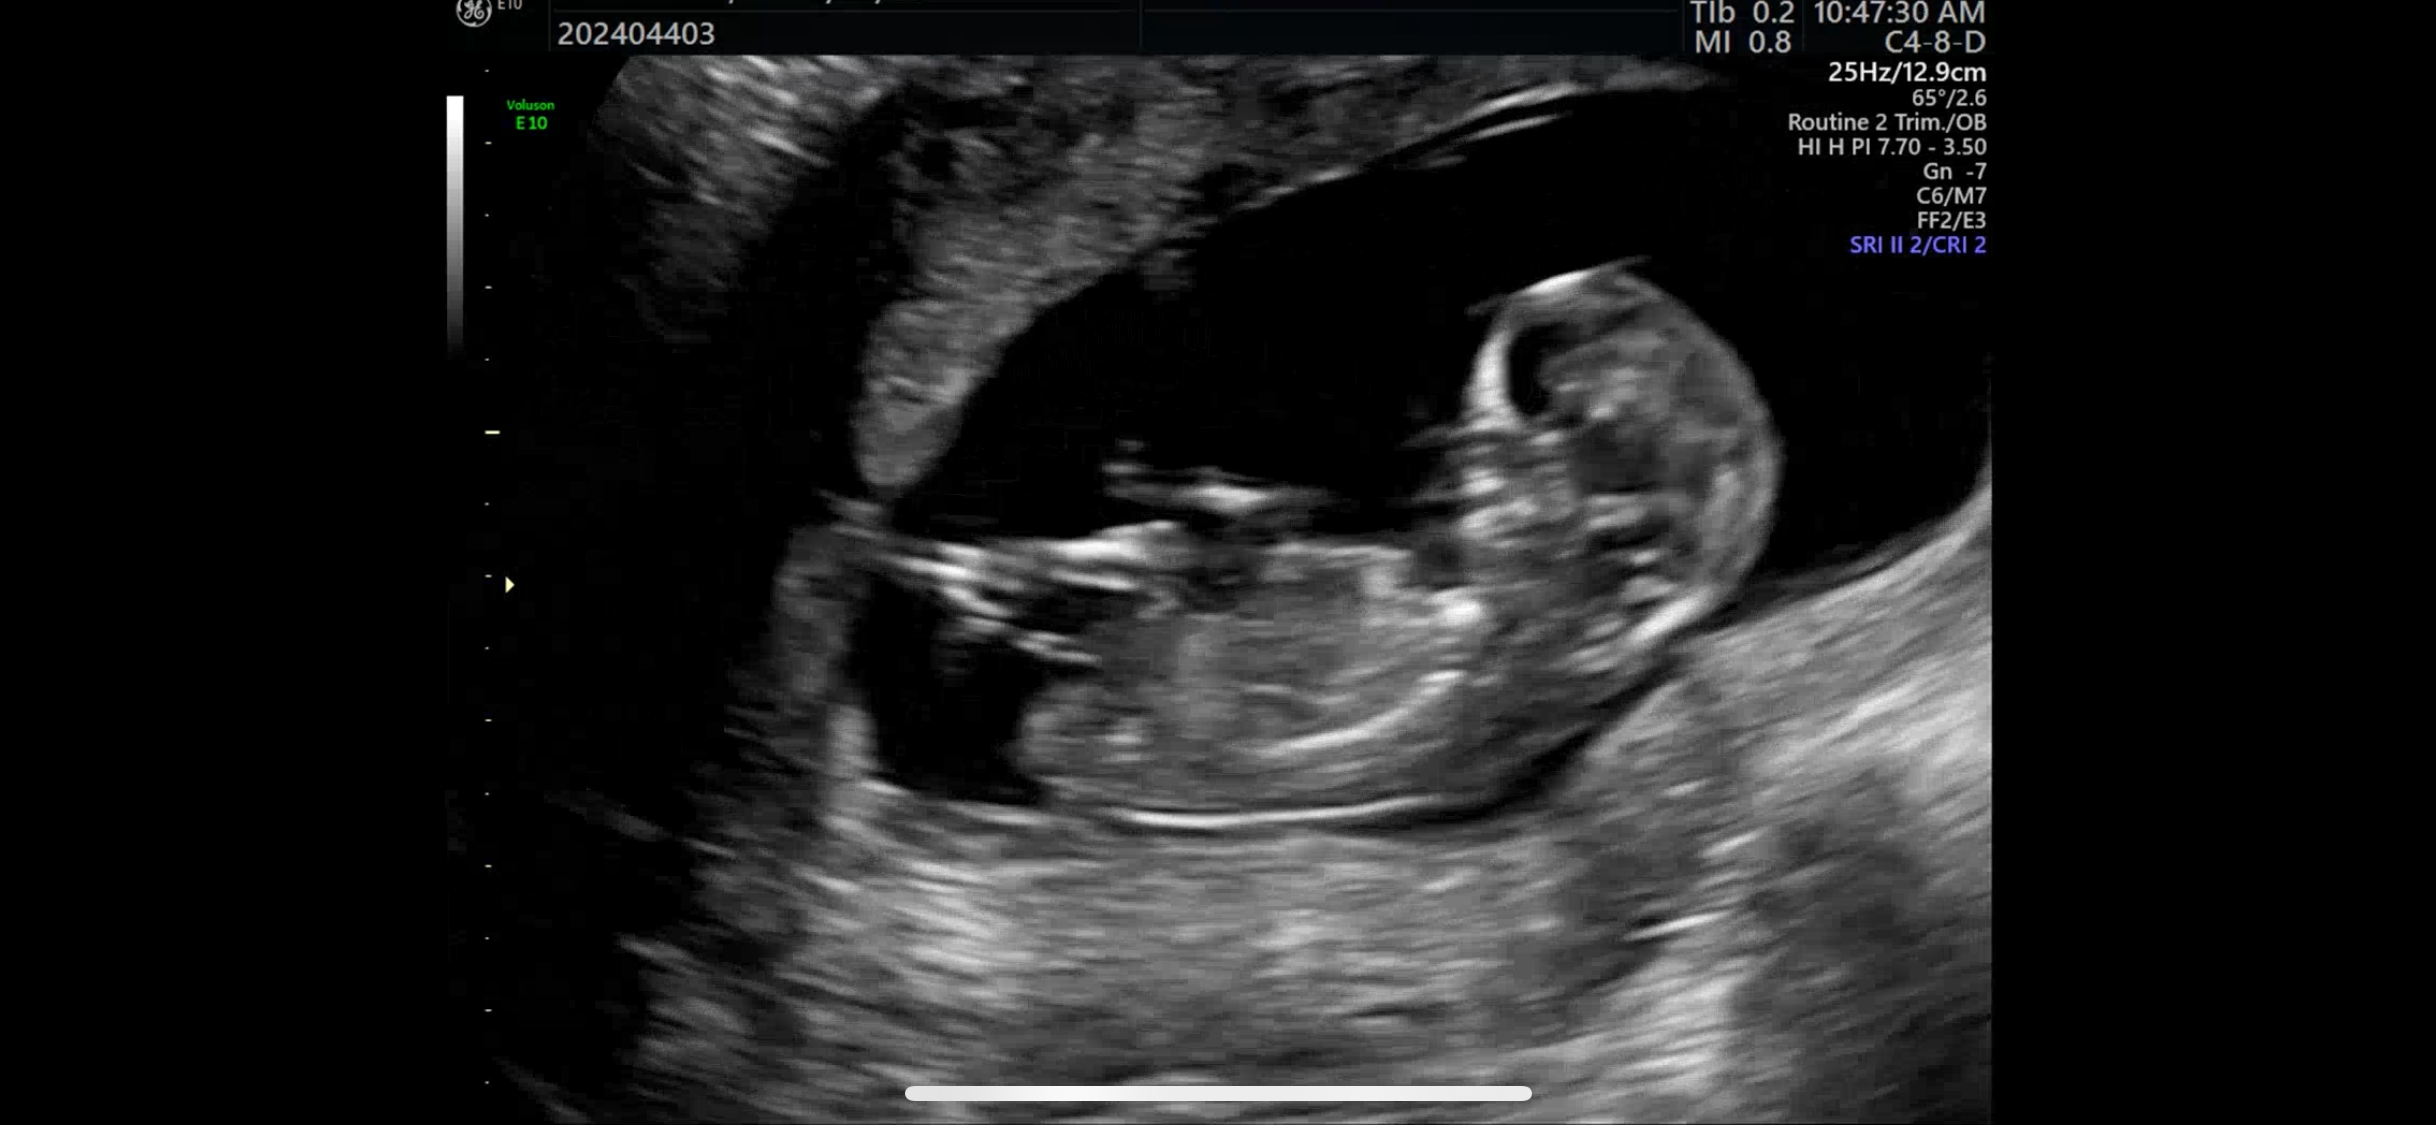

12주차0일 초음파 각도법 봐주세요!!

성별 궁금해요 ㅠㅠㅠ